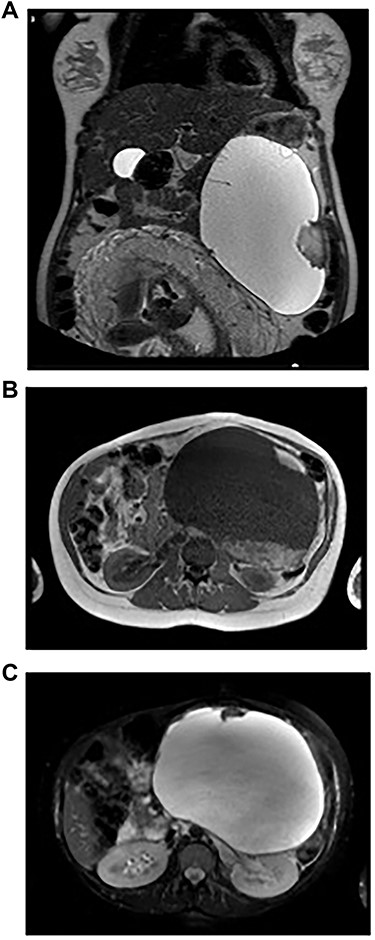

A 32-year-old woman at 31 weeks of pregnancy was referred to our hospital due to an abdominal mass detected during routine check-up. She had no notable medical history. The third-trimester routine abdominal ultrasound revealed the presence of a cystic lesion in the left upper abdomen, which was not noted in previous ultrasounds. Further evaluation with magnetic resonance imaging (MRI) revealed a complex cystic lesion (21 × 13 × 14 cm) arising in the left quadrant of the abdomen, involving the tail of the pancreas (Fig. 1a). The cyst had two solid components, the largest one with 5.2 cm (Fig. 1b). There were also a few septa inside the cystic mass (Fig. 1a and c). The diagnostic hypotheses were an idiopathic retroperitoneal hematoma, a pancreatic MCN or retroperitoneal cystic lesion. Despite its large volume, the patient did not present complaints and physical examination revealed normal.

Imaging studies. A: Abdominopelvic T2-weighted coronal MRI – Voluminous left supramesocolic cystic formation (24 cm × 17 cm × 13 cm), with well-defined contours and small septa and parietal vegetation inside. B: Abdominopelvic T1-weighted axial MRI – The lesion with a solid component hyperintense on T1-weighted imaging, translating eventual area of haemorrhage. C: Abdominopelvic T2-weighted axial MRI – The lesion pushed the stomach to the right and the spleen upward, as well as the kidney to the back, apparently without direct invasion of these structures.

The delivery was anticipated to 37-week gestation due to fetal growth restriction caused by increased tumour size, and the patient had a vaginal non-complicated delivery. At that point, the tumour measured 24 × 17 × 13 cm (longitudinal diameter/transverse diameter/anteroposterior axis).